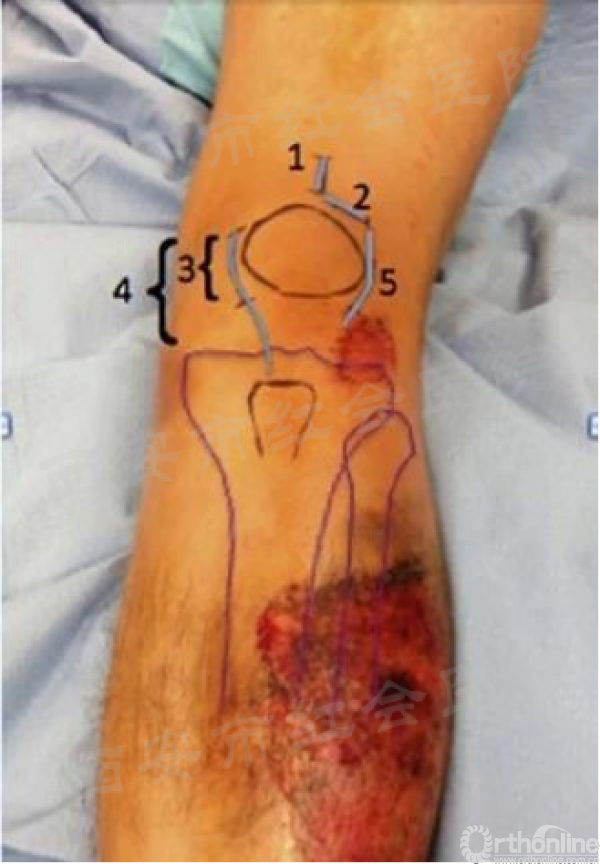

P,髌旁;EP,关节外髌旁;SP,髌上;LP,外侧髌旁

1. 髌上经髌韧带入路/(髌上入路);2.髌韧带旁入路(髌旁入路);3.内侧有限切口髌韧带旁入路(髌旁入路);4.内侧延长切口髌韧带旁入路(关节外髌旁入路);5.外侧髌韧带旁入路(关节外髌旁入路)

髌外侧入路

仰卧于可透视手术床,铺巾前小腿下垫楔形垫。沿髌骨、髌腱外侧做一长约5cm的弧形切口,切开髌腱外侧支持带,牵开并保护脂肪热,触摸入点,克氏针定位,透视证实,用套筒将髌骨和髌腱往内侧推移,开口,置入导针,随后对骨折进行复位,再按照标准流程植入髓内钉。